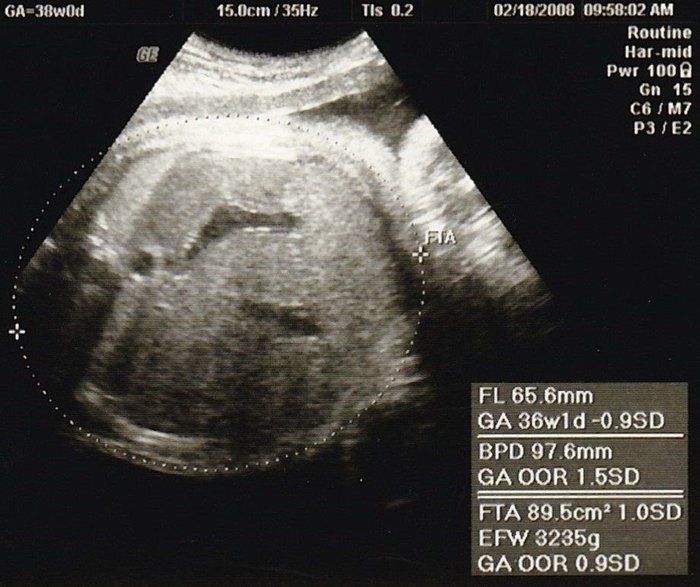

こぢんまり子さんの妊娠38週目のエコー写真 出産直前!

出産前日のエコーです。真ん中の薄い線が背骨、上のところが腰だと思います。この頃は、赤ちゃんの頭は私の骨盤の方にあり、顔を見ることはできませんでした。